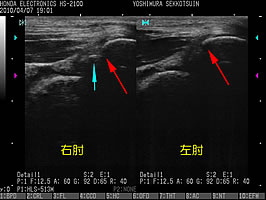

肘関節100度屈曲位での、後方からの長軸走査(↑)。右肘では、赤矢印の先が繋がっておりません。

水色矢印の先にある白い線は、本来であれば左肘関節の様に赤矢印右側の白い線まで一連に繋がっているべきですが、右肘関節は連続していません。